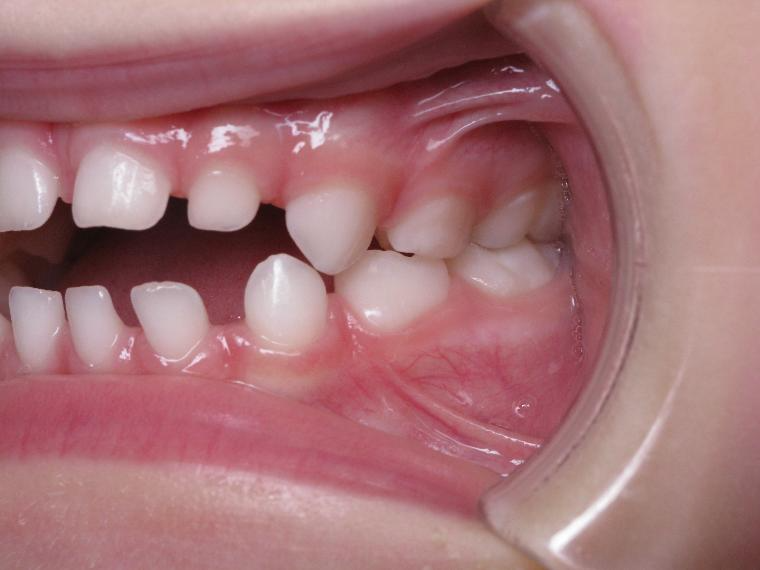

12 béance inversé droit 4 ans

inversion postérieur coté droit et espace entre les dents du haut et du bas (diastèmes)